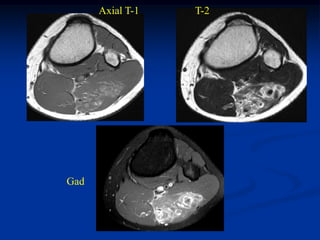

Case #1185

59 year female with

intramuscular lipoma

anterior proximal thigh

Coronal T-1 MRI

Axial T-2 MRI

at lower level

Fat subtraction MRI

showing signal void

in lipoma

Case #1185 59 yearfemale with intramuscular lipoma anterior proximal thigh Coronal T-1 MRI

• 54.

• 55.

Axial T-2 MRI atlower level

• 56.

Fat subtraction MRI showingsignal void in lipoma